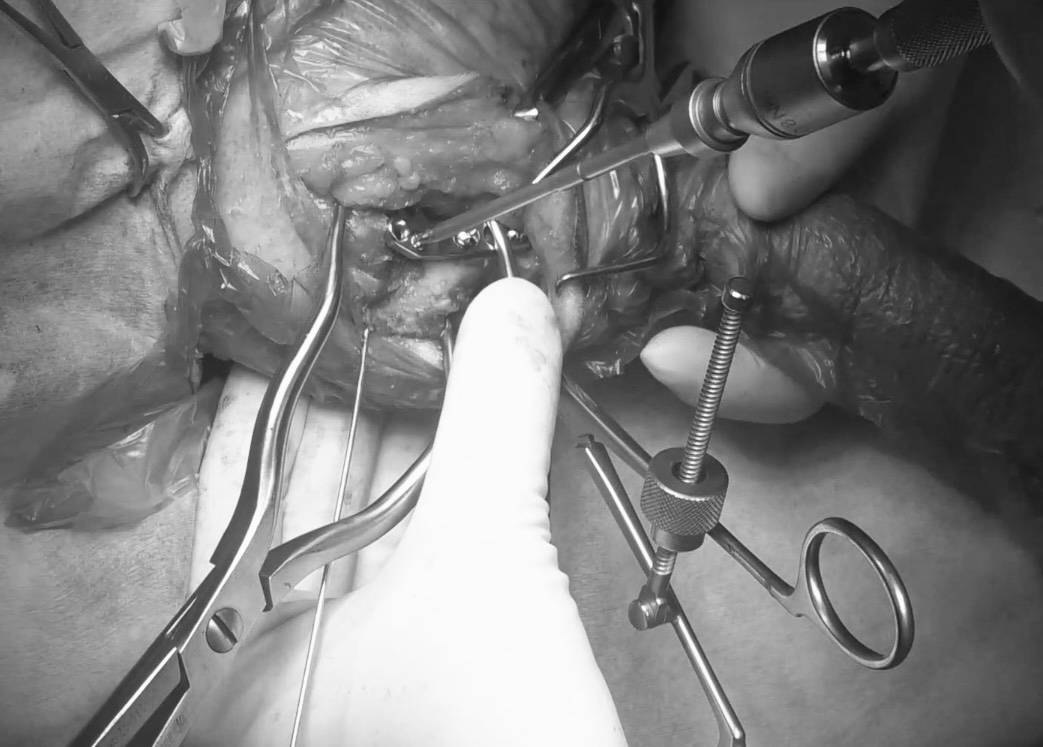

術中の様子① 断裂した前十字靭帯と半月板の確認、除去

術中の様子② 骨切り

術中の様子③ プレーティング